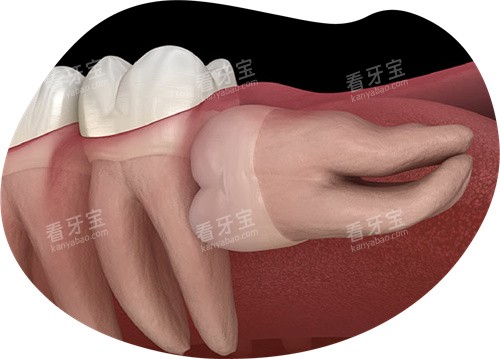

医生推了推眼镜:"这个要看具体情况。如果是普通牙齿,我们一般会建议先尝试修补。但智齿比较特殊,位置靠后很难清洁,即使补了也很容易再次蛀坏。"

医生看出了我的恐惧,耐心解释道:"补是可以补,但你要想清楚几点:头一,智齿补牙难度大,费用也高;第二,补完后你可能还是很难清洁到位;第三,如果补牙后再次蛀坏,到时候情况可能更严峻。"

我表姐的经历让我印象深刻。她的智齿也是先烂了个小洞,当时选择了补牙。结果半年后,补的材料脱落了,牙齿烂得更严峻,然后不得不拔掉,还引发了轻微的感染,多受了不少罪。

"年轻人,你这颗智齿已经蛀到接近神经了,而且位置不正,清洁确实很困难。我的建议是拔除,虽然听起来可怕,但长远来看对你更好。"